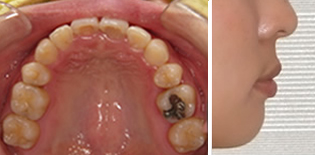

治療前-治療後

上顎の真ん中にあった骨隆起という、余分な力がかかるとできるでっぱりがなくなってきました。

歯並びの幅が広がって、きれいなU字型になってきました。これが本来の歯列の形です。

引っ込んでいた下顎が自然に前に出て、きれいな横顔になりました。